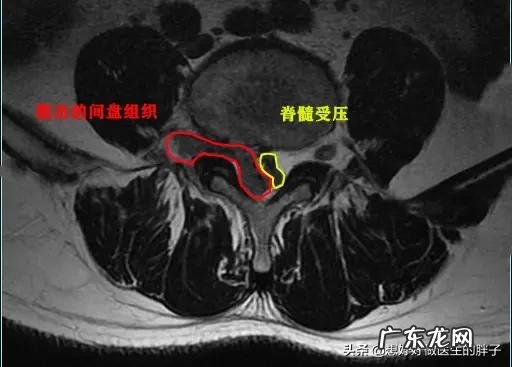

腰椎间盘突出这个疾病有一个特点,那就是很多时候影像学上的表现和患者的症状之间有差别 。在临床上确实有一部分患者,核磁、ct有严重的腰椎间盘脱出、甚至游离的影像学表现(腰椎间盘掉到了椎管里),但是却没什么特殊症状,比如下图这个患者:

这是本人的一个患者,他本身就有腰椎间盘突出,但是不重,后来由于错误的搬动重物以后诱发剧烈的腰痛,不能正常睡觉,只能坐着才能减轻腰部以及肢体的疼痛、和麻木,后来给与其进行了椎管麻醉以后,才能平卧进行核磁,当时显示椎间盘突出属于侧方突出,压迫到了神经,单纯的看检查肯定是手术适应症 。